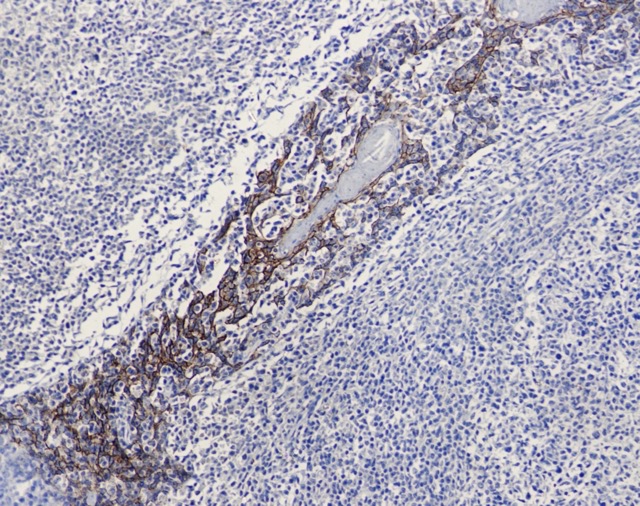

• Immunohistochemistry analysis of paraffin-embedded Human tonsils using ECadherin (6B1) antibody. High-pressure and temperature Sodium Citrate pH 6.0 was used for antigen retrieval.